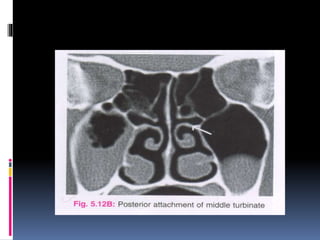

 The posterior most attachment of middle

turbinate to the palatine bone is seen